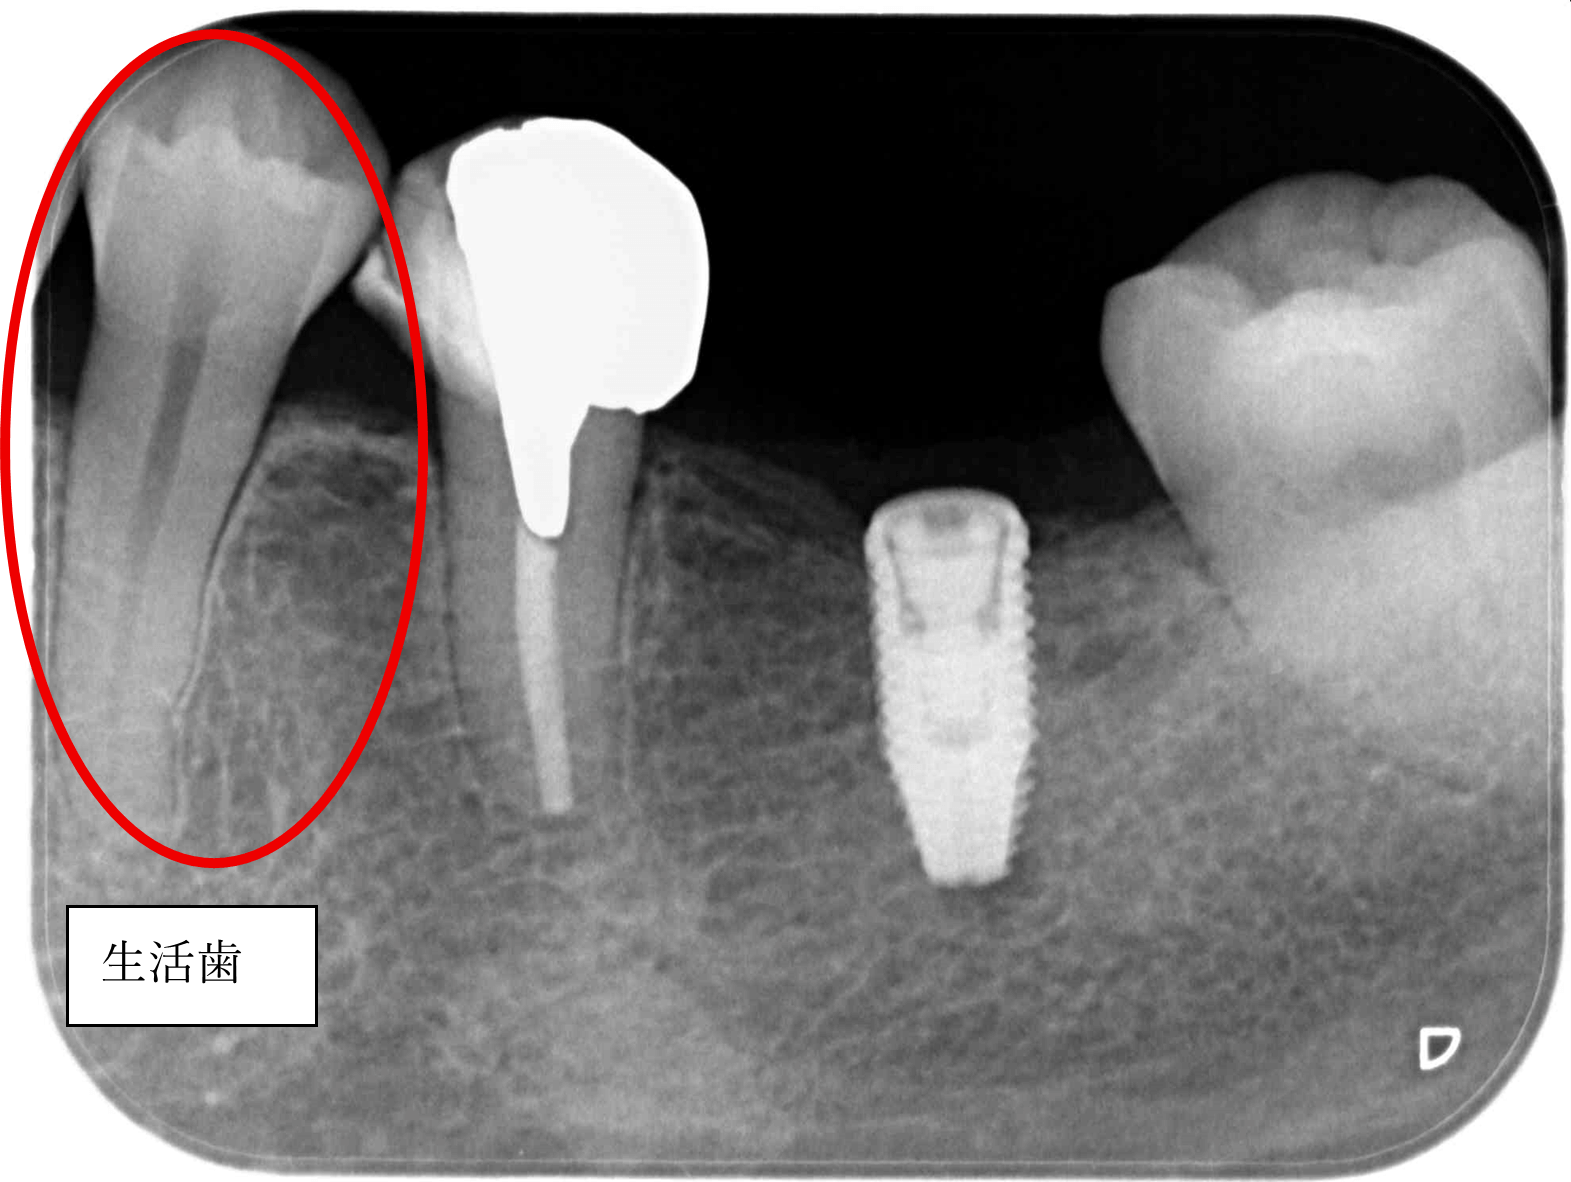

生活歯